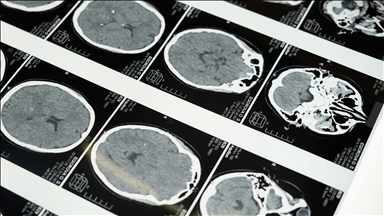

Beyin Damar Hastalıkları Hasta Derneği (BEYİNDER) Başkanı Prof. Dr. Derya Uludüz, bilimsel çalışmalarda ortaya çıkan sonuçlara göre her 100 yeni tip koronavirüs (Kovid-19) hastasından 3'ünde inme görüldüğünü belirterek, "Salgın hastalık döneminde önlemlerimizi sıkılaştırılmalıyız ve kişisel olarak korunmayı ciddiye almalıyız." dedi.

Tüm dünyada milyonlarca kişiyi etkisi altına alan Kovid-19'un, solunum yollarının yanı sıra inmeye de yol açtığını gösteren kanıtların ortaya çıkarıldığına dikkati çeken Uludüz, tehlikenin henüz geçmediğini, 65 yaş üstü ve kronik hastalığa sahip kişilerin, gençlere göre daha büyük risk altında olduğunu hatırlattı.

"Bilimsel çalışmalarda ortaya çıkan sonuçlara göre her 100 korona hastasından 3'ünde inme görülüyor. Kışın kapıya dayandığı şu günlerde salgın hastalık tehlikesiyle yaşam şeklimiz o kadar değişti ki en önemli inme risk faktörü olan yüksek tansiyon, şeker hastalığı, yüksek kolesterol, fazla kilo, sigara ve hareketsizlik durumlarını kontrol etmek çok güç hale geldi. Salgın hastalık döneminde önlemlerimizi sıkılaştırılmalıyız ve kişisel olarak korunmayı ciddiye almalıyız."

Toplumda, inmenin sıklıkla 65 yaş üstünde görüldüğü gibi bir yanlış algının olduğunu ifade eden BEYİNDER Başkan Yardımcısı Doç. Dr. Dilcan Kotan da "Artık gençlerde de inmeye sıkça rastlıyoruz. Salgında nörologlar olarak, kronik hastalığı olanlarda daha fazla olmak üzere genç yaş dahil, tüm yaş gruplarında inmeyi sıkça gördük. İngiltere'de yapılan 2 bin vakanın incelendiği bir araştırmaya göre koronavirüsün gençlerde normalden çok daha yüksek oranda inmeye yol açtığı ortaya kondu." dedi.